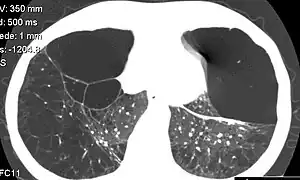

| CT scan of the lung showing bullae in the lower lung lobes of a subject with type alpha-1-antitrypsin deficiency. There is also increased lung density in areas with compression of lung tissue by the bullae. | |